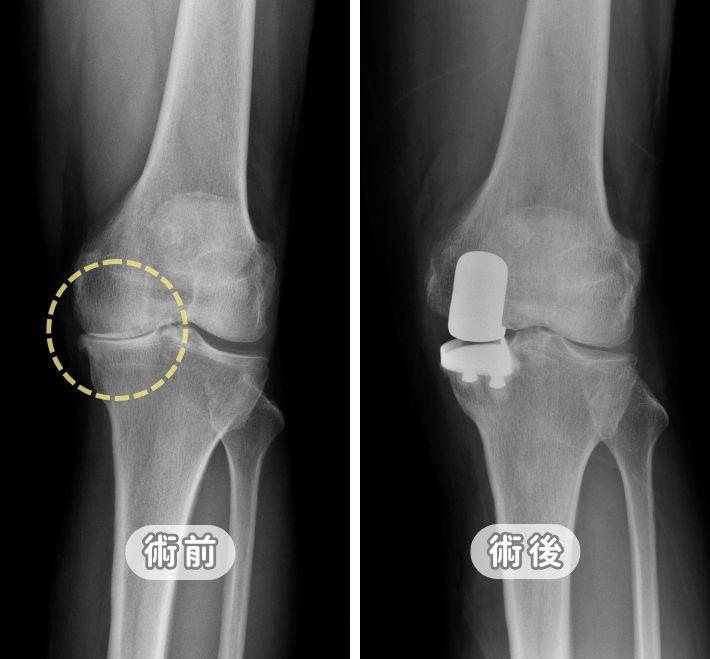

【膝關節退化】一定要換膝?免開刀治療條件與退化痛自救法

膝蓋痛一定要換關節嗎?張建鈞主任詳解膝關節退化 K-L 四階段診斷。從初期的減重、股四頭肌訓練,到 PRP 與羊膜生長因子注射,本文提供完整階梯式療法。針對重度退化,深入對比「半膝」與「全膝」置換優劣,並解析 ROSA Knee 機器人手臂如何達成 0.1 公分精準骨切除,助您術後 24 小時下床,重拾行動尊嚴。

微創膝關節置換手術全攻略:ROSA Knee 機器人手臂導航的精準醫療-退化性膝關節炎治療新方法

膝蓋痛一定要換全膝嗎?解析 ROSA Knee 3D 機器人手臂導航技術,將手術誤差降至 0.005 公分,精準平衡韌帶並保留肌肉組織。內含微創手術費用預算、ROSA 與傳統手術對照表、24小時快速康復流程,助您重拾行動自由,延長人工關節壽命。

膝蓋退化一定要換全膝?UKA半膝人工關節全攻略:置換條件與退化痛自救法

膝蓋痛一定要換全膝嗎?專業醫師解析「微創半膝人工關節置換術 (UKA)」。僅針對局部磨損修復,完整保留十字韌帶與自體骨,傷口小且術後當天即可下床。內含 UKA 與 HTO 手術對照表、術後復健與常見問題,助您精準精準找回行動力。